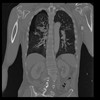

32 PULMON,CE,Coronal,3.000,PULMON,Coronal,